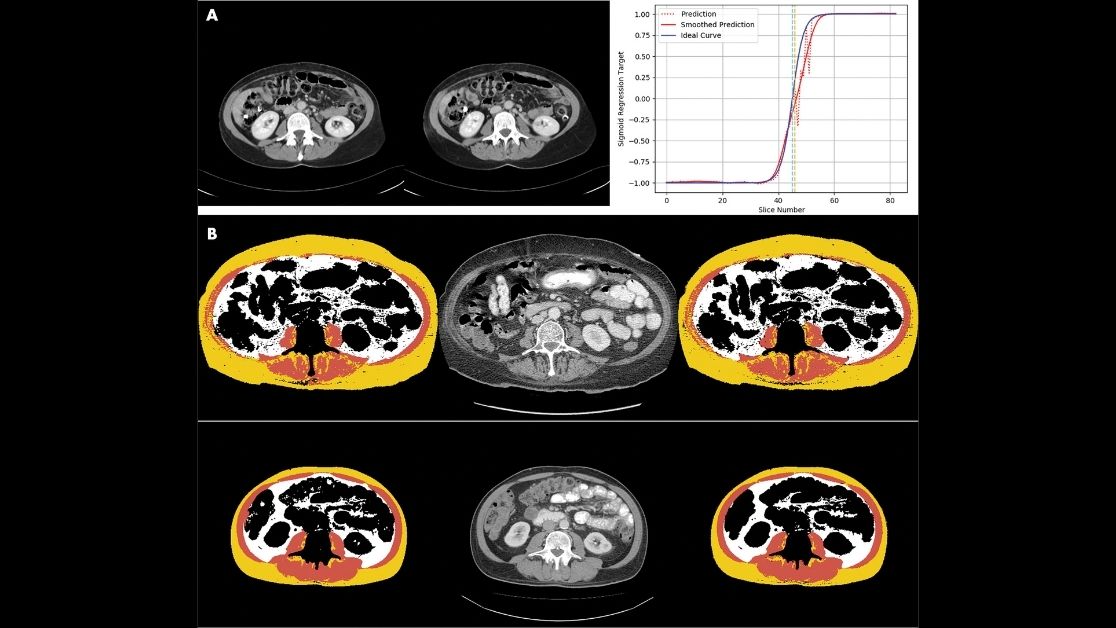

Magudia et al use fully automated deep learning at CT to show how body composition varies by age, race & sex. https://t.co/vMipcP6RSC

@KMagudia @kpa_kathy @F_Fintelmann_MD @NandMiskinMD @MRosenthalMDPhD @UCSFimaging @BWHRadiology @Clindatsci @BrighamWomens @MGHImaging @DanaFarber

Outstanding work @KMagudia @MRosenthalMDPhD. Thank for allowing me to be part of this seminal work.

In our @radiology_rsna paper, we 1) demonstrate a fully automated pipeline using DL for CT-based body composition analysis, 2) establish reference curves, & 3) show that normalized body composition values can predict 2 year survival. @MRosenthalMDPhD

https://t.co/vdsc4aX0vk